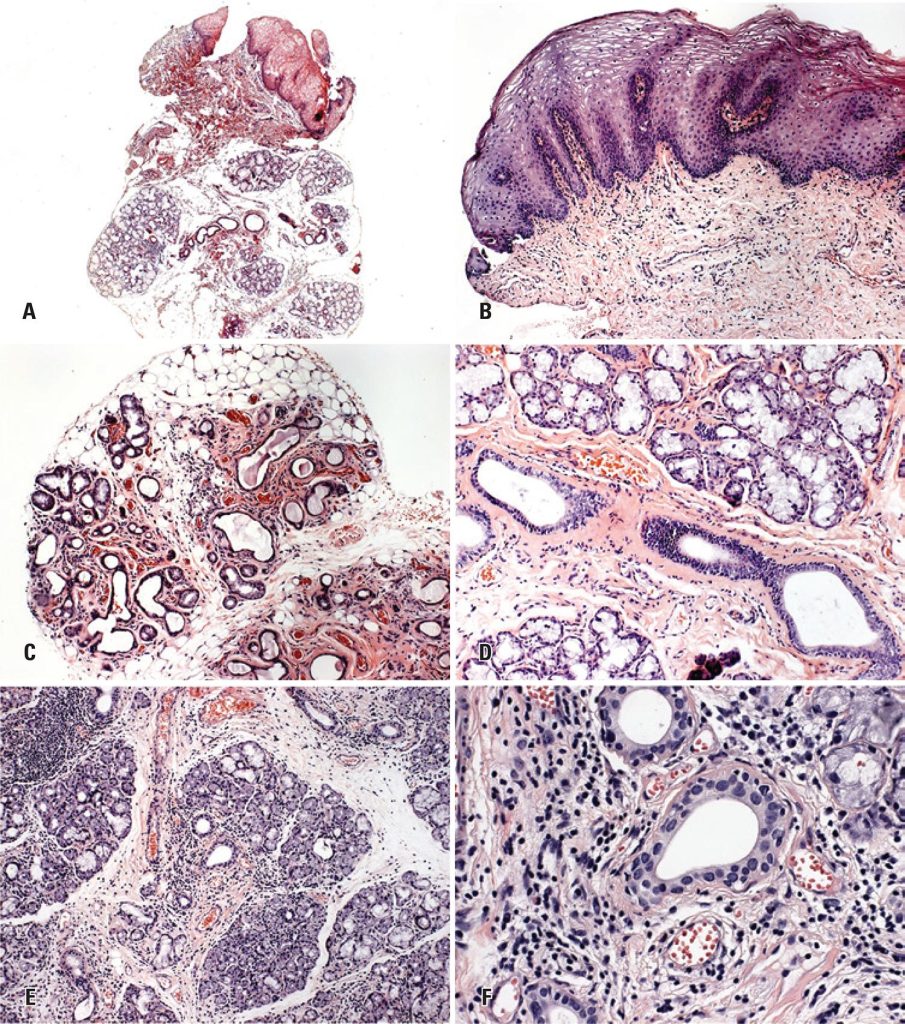

Forty-one specimens containing both oral mucosa and salivary glands were analyzed in slides stained with hematoxylin-eosin. The histological specimens were blindly examined by two trained pathologists using criteria recommended for the histopathologic diagnosis of chronic graft-versus-host disease proposed by the National Institutes of Health Consensus. The clinical classification of chronic graft-versus-host disease was correlated with analysis of slides. Results: Our data showed that the epithelium was involved in 39/41 specimens, presenting acanthosis (29/70.7%), exocytosis of lymphocytes (29/70.7%), thickening of basal lamina (29/70.7%), and apoptosis (15/36.6%). Connective tissue presented interstitial inflammatory infiltrate (38/92.7%). Minor salivary glands showed periductal fibrosis (38/92.7%), mixed periductal inflammatory infiltrate (32/78%), ductal ectasia (30/73.2%), lymphocytes around and into acinar units (30/73.2%), and interstitial fibrosis (29/70.7%). The most common clinical manifestations were lichenoid aspect (40/97.6%), complaints of sensitivity to oral feeding (38/92.7%), and dry mouth sensation (36/87.8%).